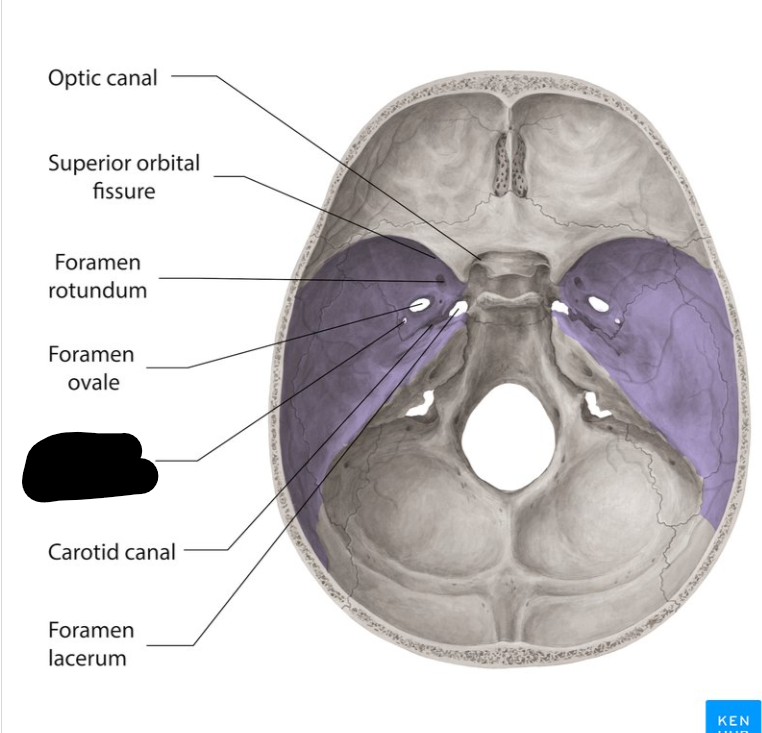

Middle cranial fossa

Foramen rotandum

Foramen ovale

Foramen lacerum

Foramen spinosum

Superior orbital fissure

Optic canal

Carotid canal